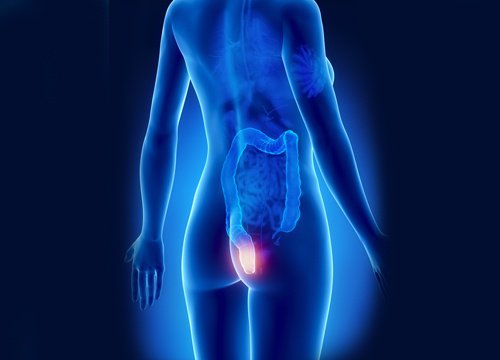

치질 자연요법은 불편하고 고통스러운 질환으로 고생하는 사람들에게 큰 도움이 된다. 치질은 염증을 일으켜 항문 벽에 닿는 종괴를 생성하는 항문 정맥의 염증이다. 대개 출혈, 염증, 가려움증, 통증과 같은 불쾌한 증상들을 동반한다.